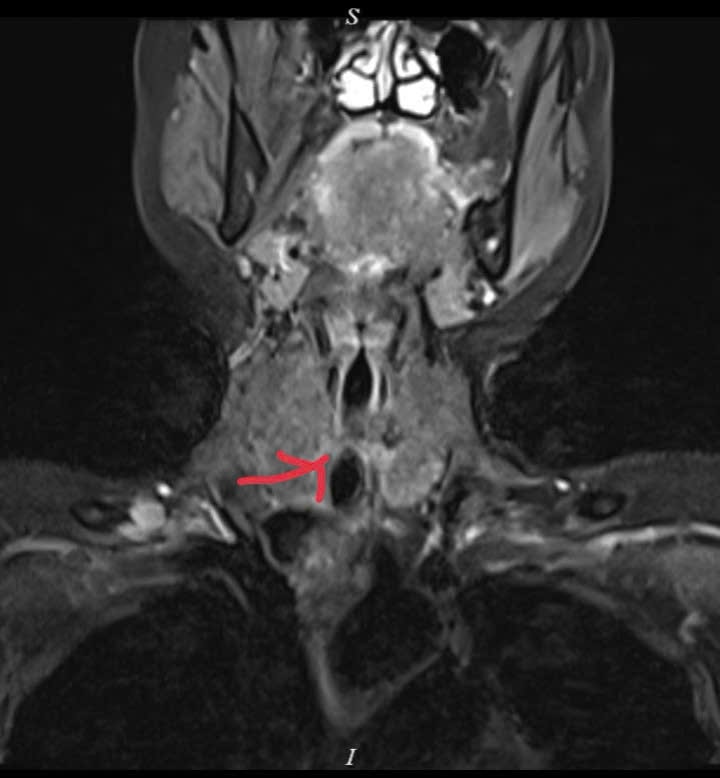

Hình ảnh khối u chèn ép gây hẹp khít đường thở của bệnh nhân.

Khối u nằm sát thanh quản, ngay đoạn trên của khí quản, khiến việc điều trị trở nên đặc biệt phức tạp. Đây là vùng giải phẫu hẹp, tập trung nhiều cấu trúc quan trọng liên quan đến hô hấp, phát âm và nuốt.

Bệnh nhân nhập viện trong tình trạng khó thở kéo dài, thở khò khè nhiều tháng nhưng trước đó chưa xác định được nguyên nhân. Sau khi tiếp nhận, các bác sĩ Trung tâm Ung bướu - Bệnh viện C Đà Nẵng, dưới sự chỉ đạo của Giám đốc Trung tâm – BS CKII. Võ Trung Nghĩa đã đánh giá toàn diện, chỉ định các phương tiện chẩn đoán chuyên sâu và phát hiện khối u nằm trong khí quản – vị trí rất nguy hiểm vì chỉ cần bít tắc thêm một phần nhỏ cũng có thể đe dọa tính mạng.